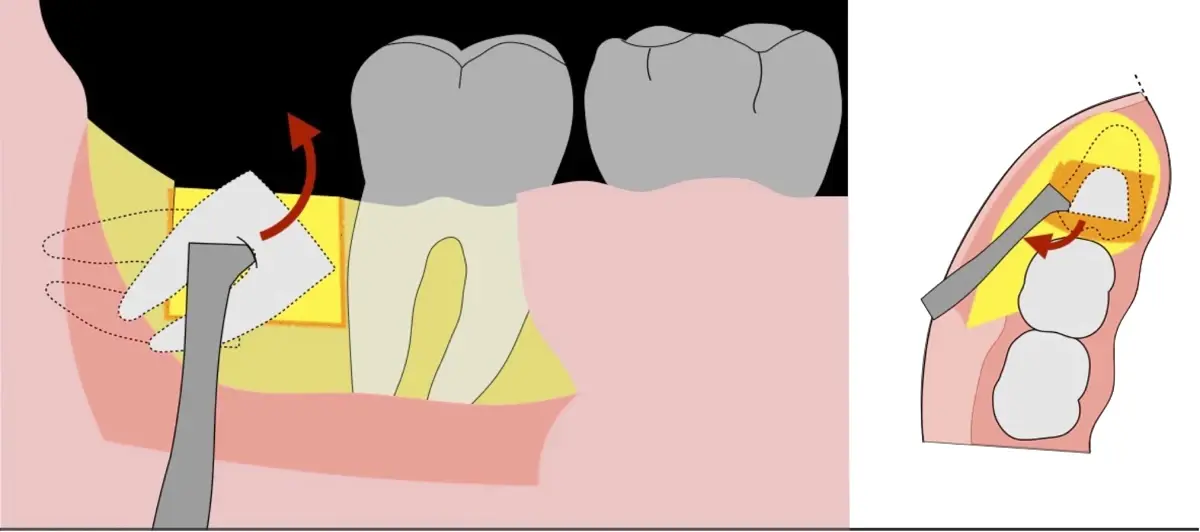

El procedimiento se inicia colocando anestesia troncular para bloqueo del nervio dentario inferior y sus ramas. Luego, se establecerá el diseño de acceso según la disposición de la molar a extraer. Para fines didácticos, se explicará cómo se realizaría la extracción de la molar de la Figura 1: se realiza una incisión horizontal a nivel de la zona retromolar hasta llegar a distal de la segunda molar, continuándose con una incisión intrasurcular hasta mesial de la segunda molar, finalizando con una incisión vertical a espesor total hasta llegar a la línea mucogingival (Figura 2).